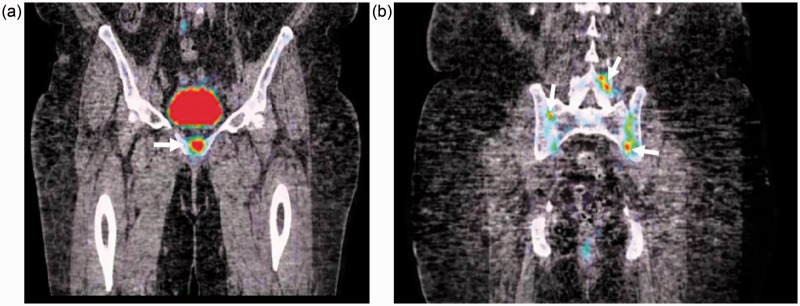

在这个病例报告中,我们描述了一个“罕见”的轴性痛风性关节病,患者是一位69岁的女性,患有双侧坐骨神经痛,并通过常规x线摄影、CT扫描、磁共振成像、骨显像和PET-CT进行了全面评估。轴性痛风关节病应包括在慢性腰痛的鉴别诊断中,主要是当存在痛风的几个危险因素时。

In this case report, we describe an "uncommon" case of axial gouty arthropathy in a 69-year-old woman with bilateral sciatica that was thoroughly evaluated with conventional radiography, CT scan, magnetic resonance imaging, bone scintigraphy, and PET-CT. Axial gouty arthropathy should be included in the differential diagnosis of chronic low back pain, mainly when several risk factors for gout are present.